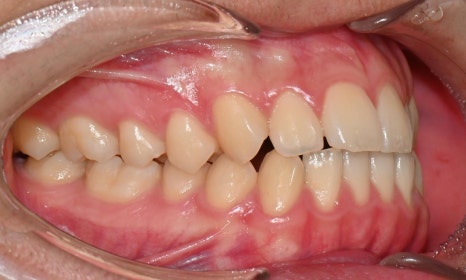

정밀 검진 결과, 하악 치열이 좌측으로 틀어져 있었고 그로 인해 위아래 치아 중심선이 일치하지 않았습니다. 아래 치열이 전체적으로 전방 위치하여 아래 입술 돌출이 더 도드라져 보이는 상태였습니다. 그리고 상악궁이 하악궁보다 좁아서 앞니 부위 일부 반대로 물리는 치아 교합도 관찰되었습니다. 특히 외상 치아의 경우, 교정력 적용시 추가적인 염증성 치근 흡수 위험이 존재하기 때문에, 치료 중 지속적인 관찰이 필수적인 상황이었습니다.

치료 시작 7개월 후 사진으로, 치아 배열 후 아래 우측에 미니스크류를 식립하여 치아 중심선을 개선하는 중으로, 교합과 치아 중심선이 많이 개선된 것을 확인할 수 있습니다.